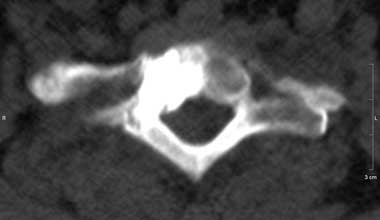

Для лечения данных заболеваний применяется «пункционная вертебропластика» происходит от трех латинских слов: пункция - прокол, вертебрум – позвонок и пластика – восстановление. Дословно он означает - восстановление позвонка путем прокола.

Под этим следует понимать восстановление формы, размеров и функции позвонка, так называемым закрытым способом, то есть, без разреза кожи и других тканей (фасций, мышц и связок). Специальная игла вводится в больной позвонок путем прокола. Через иглу в позвонок под давлением нагнетается особый костный цемент, который восстанавливает форму и размеры позвонка, а так же, придает ему повышенную прочность и восстанавливает утраченную опорную функцию.

Томограф фирмы TOSHIBA позволяет не только ставить точный диагноз, но и эффективно лечить пациентов: являясь новатором в технологии КТ, фирма TOSHIBA первая разработала возможность КТ – рентгеноскопии в реальном времени ( КТ – флюороскопия). КТ – это навигация в реальном времени, т.е. специальная флюороскопическая программа дает хирургу возможность проводить пункцию или пункционную биопсию образований, следя за продвижением иглы на экране томографа в реальном времени. Это полностью исключает нежелательное повреждение жизненно важных структур и обеспечивает точность попадания в заданную цель с точностью до 1 мм. Уже сегодня специалисты Центра Эндоскопической нейрохирургии, первыми в Украине, успешно делают бескровные пункционные операции на позвоночнике под контролем компьютерного томотрафа, так называемые пункционная вертебропластика – это когда под контролем томографа в тело поражённого позвонка вводится специальный костный цемент, который через несколько минут застывает. Это эффективный метод предупреждения и лечения патологических переломов позвонков при гормональном остеопорозе и гемангиоме тел позвонков.